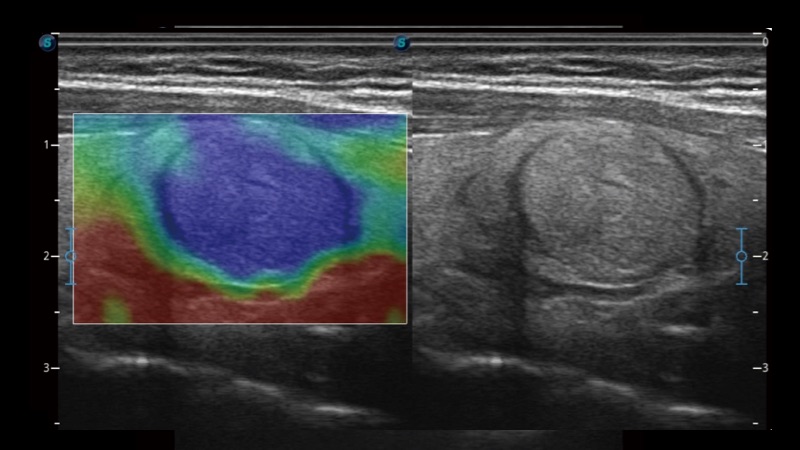

開立醫(yī)療通過不斷的技術(shù)創(chuàng)新,為大眾的生命健康提供持續(xù)關(guān)愛。P12 Plus采用全新一代超聲成像平臺,新平臺旨在將真實還原組織解剖結(jié)構(gòu)作為首要目標(biāo)。平臺采用全新集成化硬件模塊,搭載新一代芯片,系統(tǒng)性能得到大幅提升,為您的診斷提供了豐富的臨床信息。優(yōu)異的圖像表現(xiàn),豐富的探頭配置,全面的應(yīng)用功能,為您日常診斷提供了可靠的助手。

P12 Plus

彩色多普勒超聲診斷系統(tǒng)